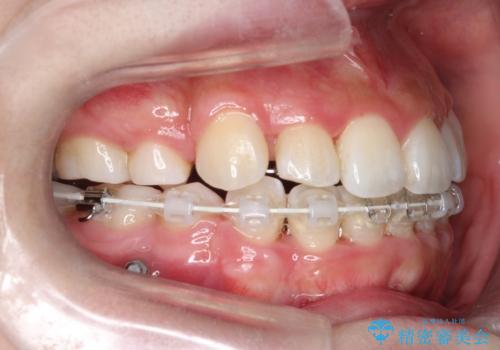

八重歯を改善!美しい口元を実現するハーフリンガル矯正

- 矯正装置

- ハーフリンガル

ハーフリンガルワイヤー矯正で治療を開始しました。

ハーフリンガル矯正は、見た目を気にせずに矯正治療ができる方法です。この治療法は、八重歯や前歯のガタツキを効果的に改善します。特徴として、ワイヤーが上の歯の裏側に装着されるため、装置が外から見えません。これにより、治療中も自然な笑顔を保ちながら安心して治療を続けることができます。歯並びの悩みを持つ方にとって、非常に魅力的な選択肢です。